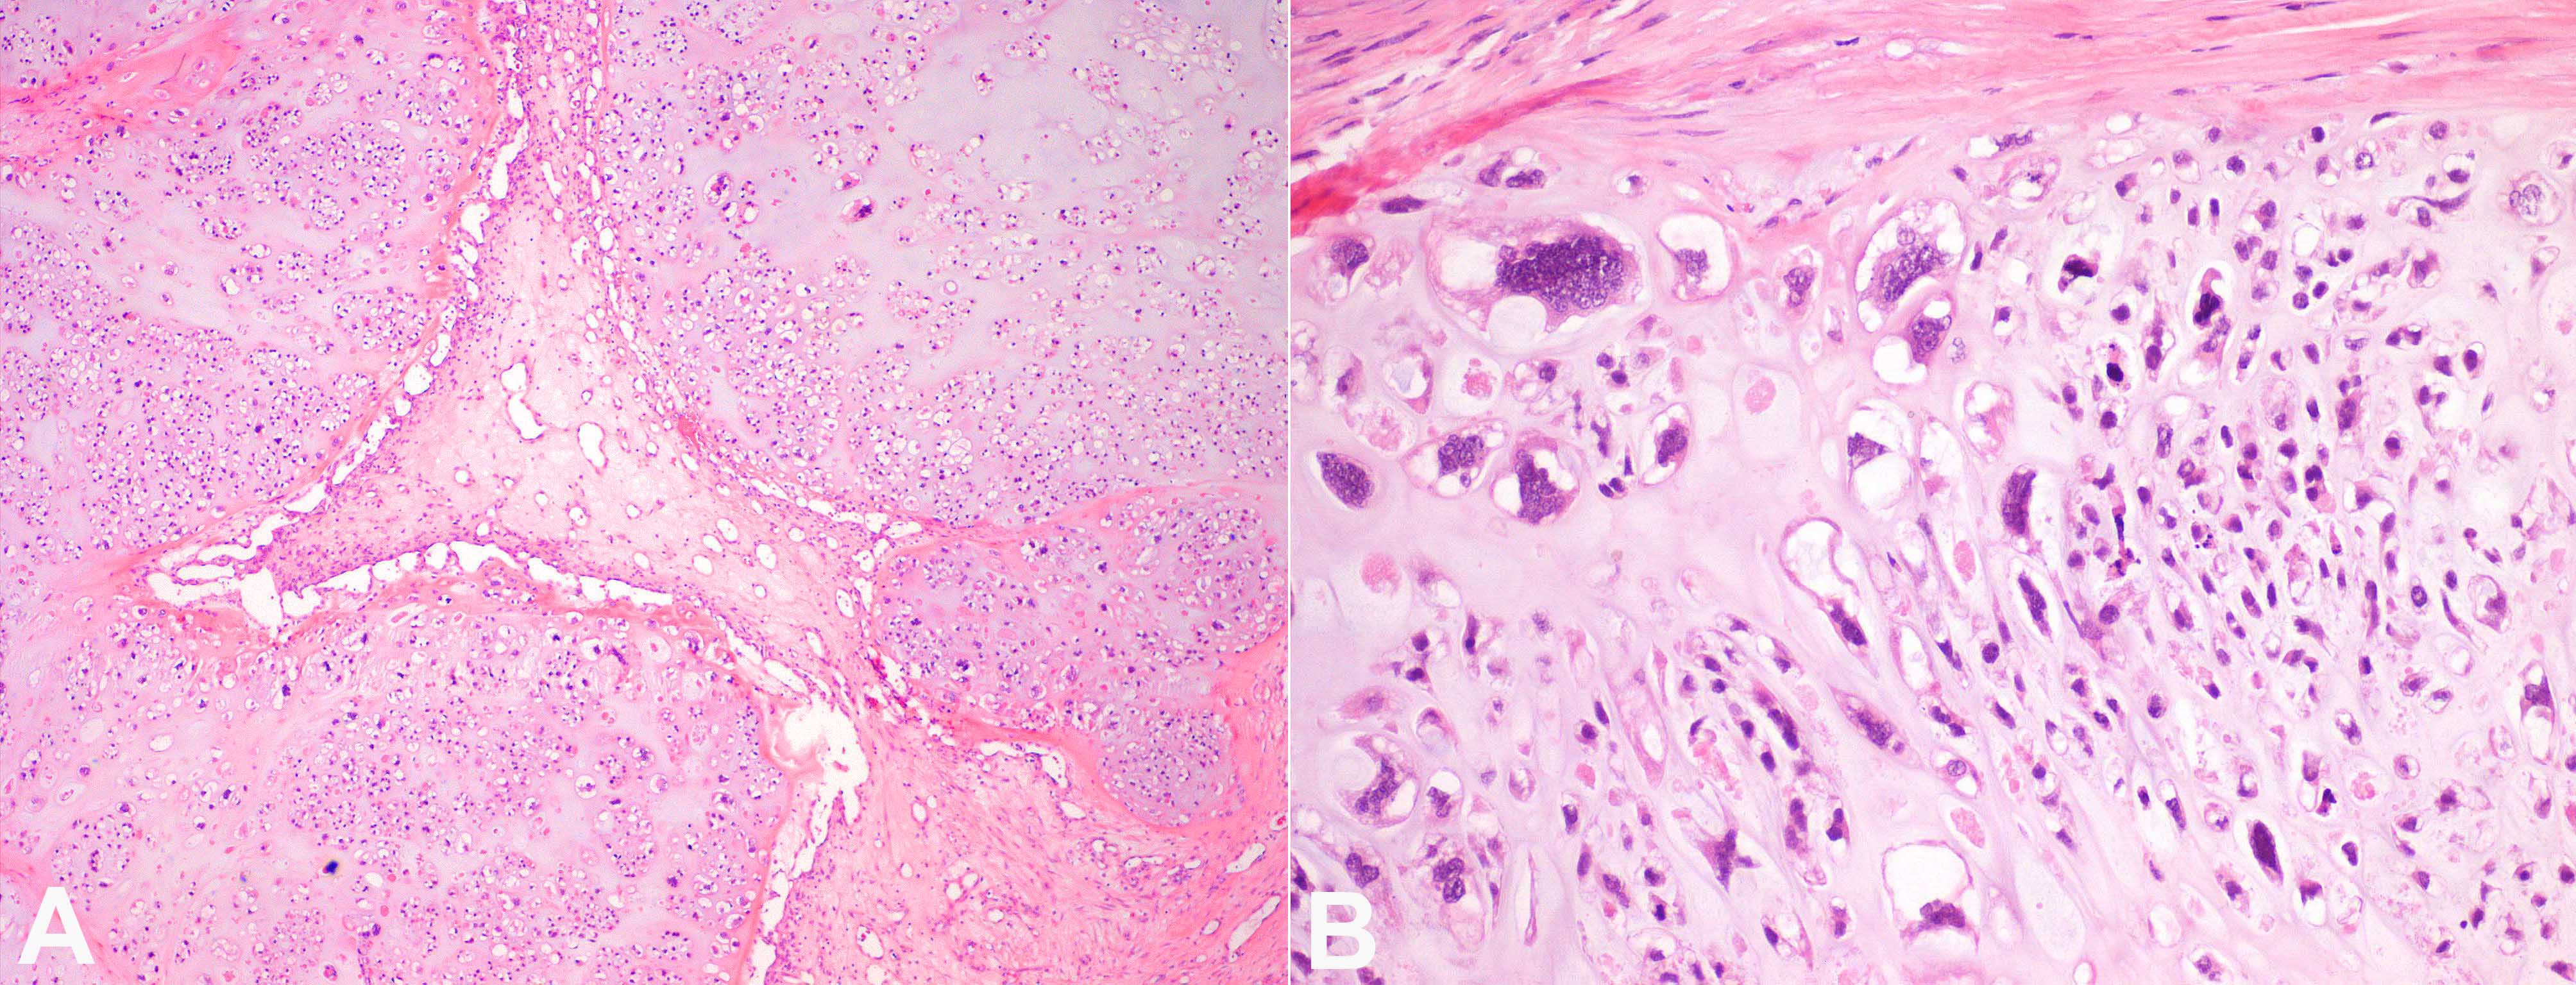

The histologic analysis reported a grade III conventional chondrosarcoma (Figure 4). Complete tumor excision with negative histologic margins was obtained. Reconstruction of the full-thickness chest wall defect was achieved with a sandwich technique of methyl methacrylate (MMA) between two layers of polypropylene mesh, sutured to the remaining ribs to maintain thoracic wall stability. It was covered with a pedicled latissimus dorsi (LD) muscle flap (Figure 5).

Preoperative planning in chest wall reconstruction is paramount and requires a methodic evaluation of the anticipated defect, considering the defect’s size and layers to repair (skeleton and soft tissue), and the preservation of potential reconstructive options without compromising the appropriate extension of tumor resection. In this case, the patient underwent resection of four ribs, which is a significant number considering the data reported in the literature (mean: three to four ribs).2,10-12,13,19 Chest skeletal support was restored with the MMA-polypropylene mesh sandwich technique while a pedicled LD muscle flap provided soft tissue coverage, in accordance with reconstructive recommendations for the number of ribs resected (four or more ribs), and the dimension and location of the defect (lateral ≥300 cm2).1,9,11 LD muscle (or musculocutaneous) flap is among the best options since it is a reliable and large flap that can be tailored to the defect.1,7,12 It has a wide arc of rotation, being particularly suited for anterior and anterolateral defects, but can be successfully used for most defect locations.1,7,11-14 Planning of the surgical incision placements for thoracotomy access is essential if a regional flap is to be used for reconstruction. Sparing the LD and serratus muscles during thoracotomy, or the pectoralis muscle in anterior resections—also avoiding the section of flap dominant pedicles—will preserve these options for subsequent reconstruction. In this patient, a large anterolateral chest wall resection with the sacrifice of local muscle flaps was needed, while vital thoracic structures were preserved, avoiding life-threatening conditions. Team planning of the thoracotomy allowed the preservation of LD and its pedicle traced near the resection margins. Preservation of the regional flaps provides an effective option, with shorter operative and recovery time, compared with the alternative free flap reconstruction. Adequate reconstruction delivers protection of the underlying viscera, improvement in respiratory mechanics that can significantly shorten ventilator requirements and hospital stay, and maintenance of thoracic shape with better cosmetic results.2,3 Our patient's length of hospital stay was 13 days (including 3 days in ICU), which is among the lowest data mentioned in the literature (11.5–20 days; 4–5 days in ICU).9-12 Chondrosarcomas usually have a better prognosis than other chest wall malignancies, with 5-year survival rates of 85%–90%.2,13,19 Histologically, they are classified into three grades (I–III), with grade III chondrosarcomas presenting as highly cellular tumors with marked pleomorphism and frequent mitoses, which are associated with lower survival rates.3 Our patient had clinical and tumoral features that could be considered poorer prognostic factors, such as being older than 50 years, having a large tumor volume (>200 cm3), grade III histology, and compression of thoracic structures.2,3,10,13 However, wide excision with clear margins stands as a main prognostic factor for long-term survival since local recurrence portends systemic metastasis and eventual tumor-related mortality.2,3 A complete tumoral excision with negative margins in addition to a successful functional and aesthetic chest wall reconstruction was accomplished in this patient. Therefore, tumoral resection must never be compromised due to concerns regarding the defect closure. A multidisciplinary approach and teamwork between thoracic and plastic surgeons are fundamental, allowing a safe and reliable one-stage tumoral resection and chest wall reconstruction with optimal oncologic outcomes and minimal patient morbidity.

The authors would like to thank Dr. Mariana Afonso from the Department of Pathological Anatomy, Portuguese Institute of Oncology - Porto, for her work on the histologic images of tumoral specimen preparation and analysis.